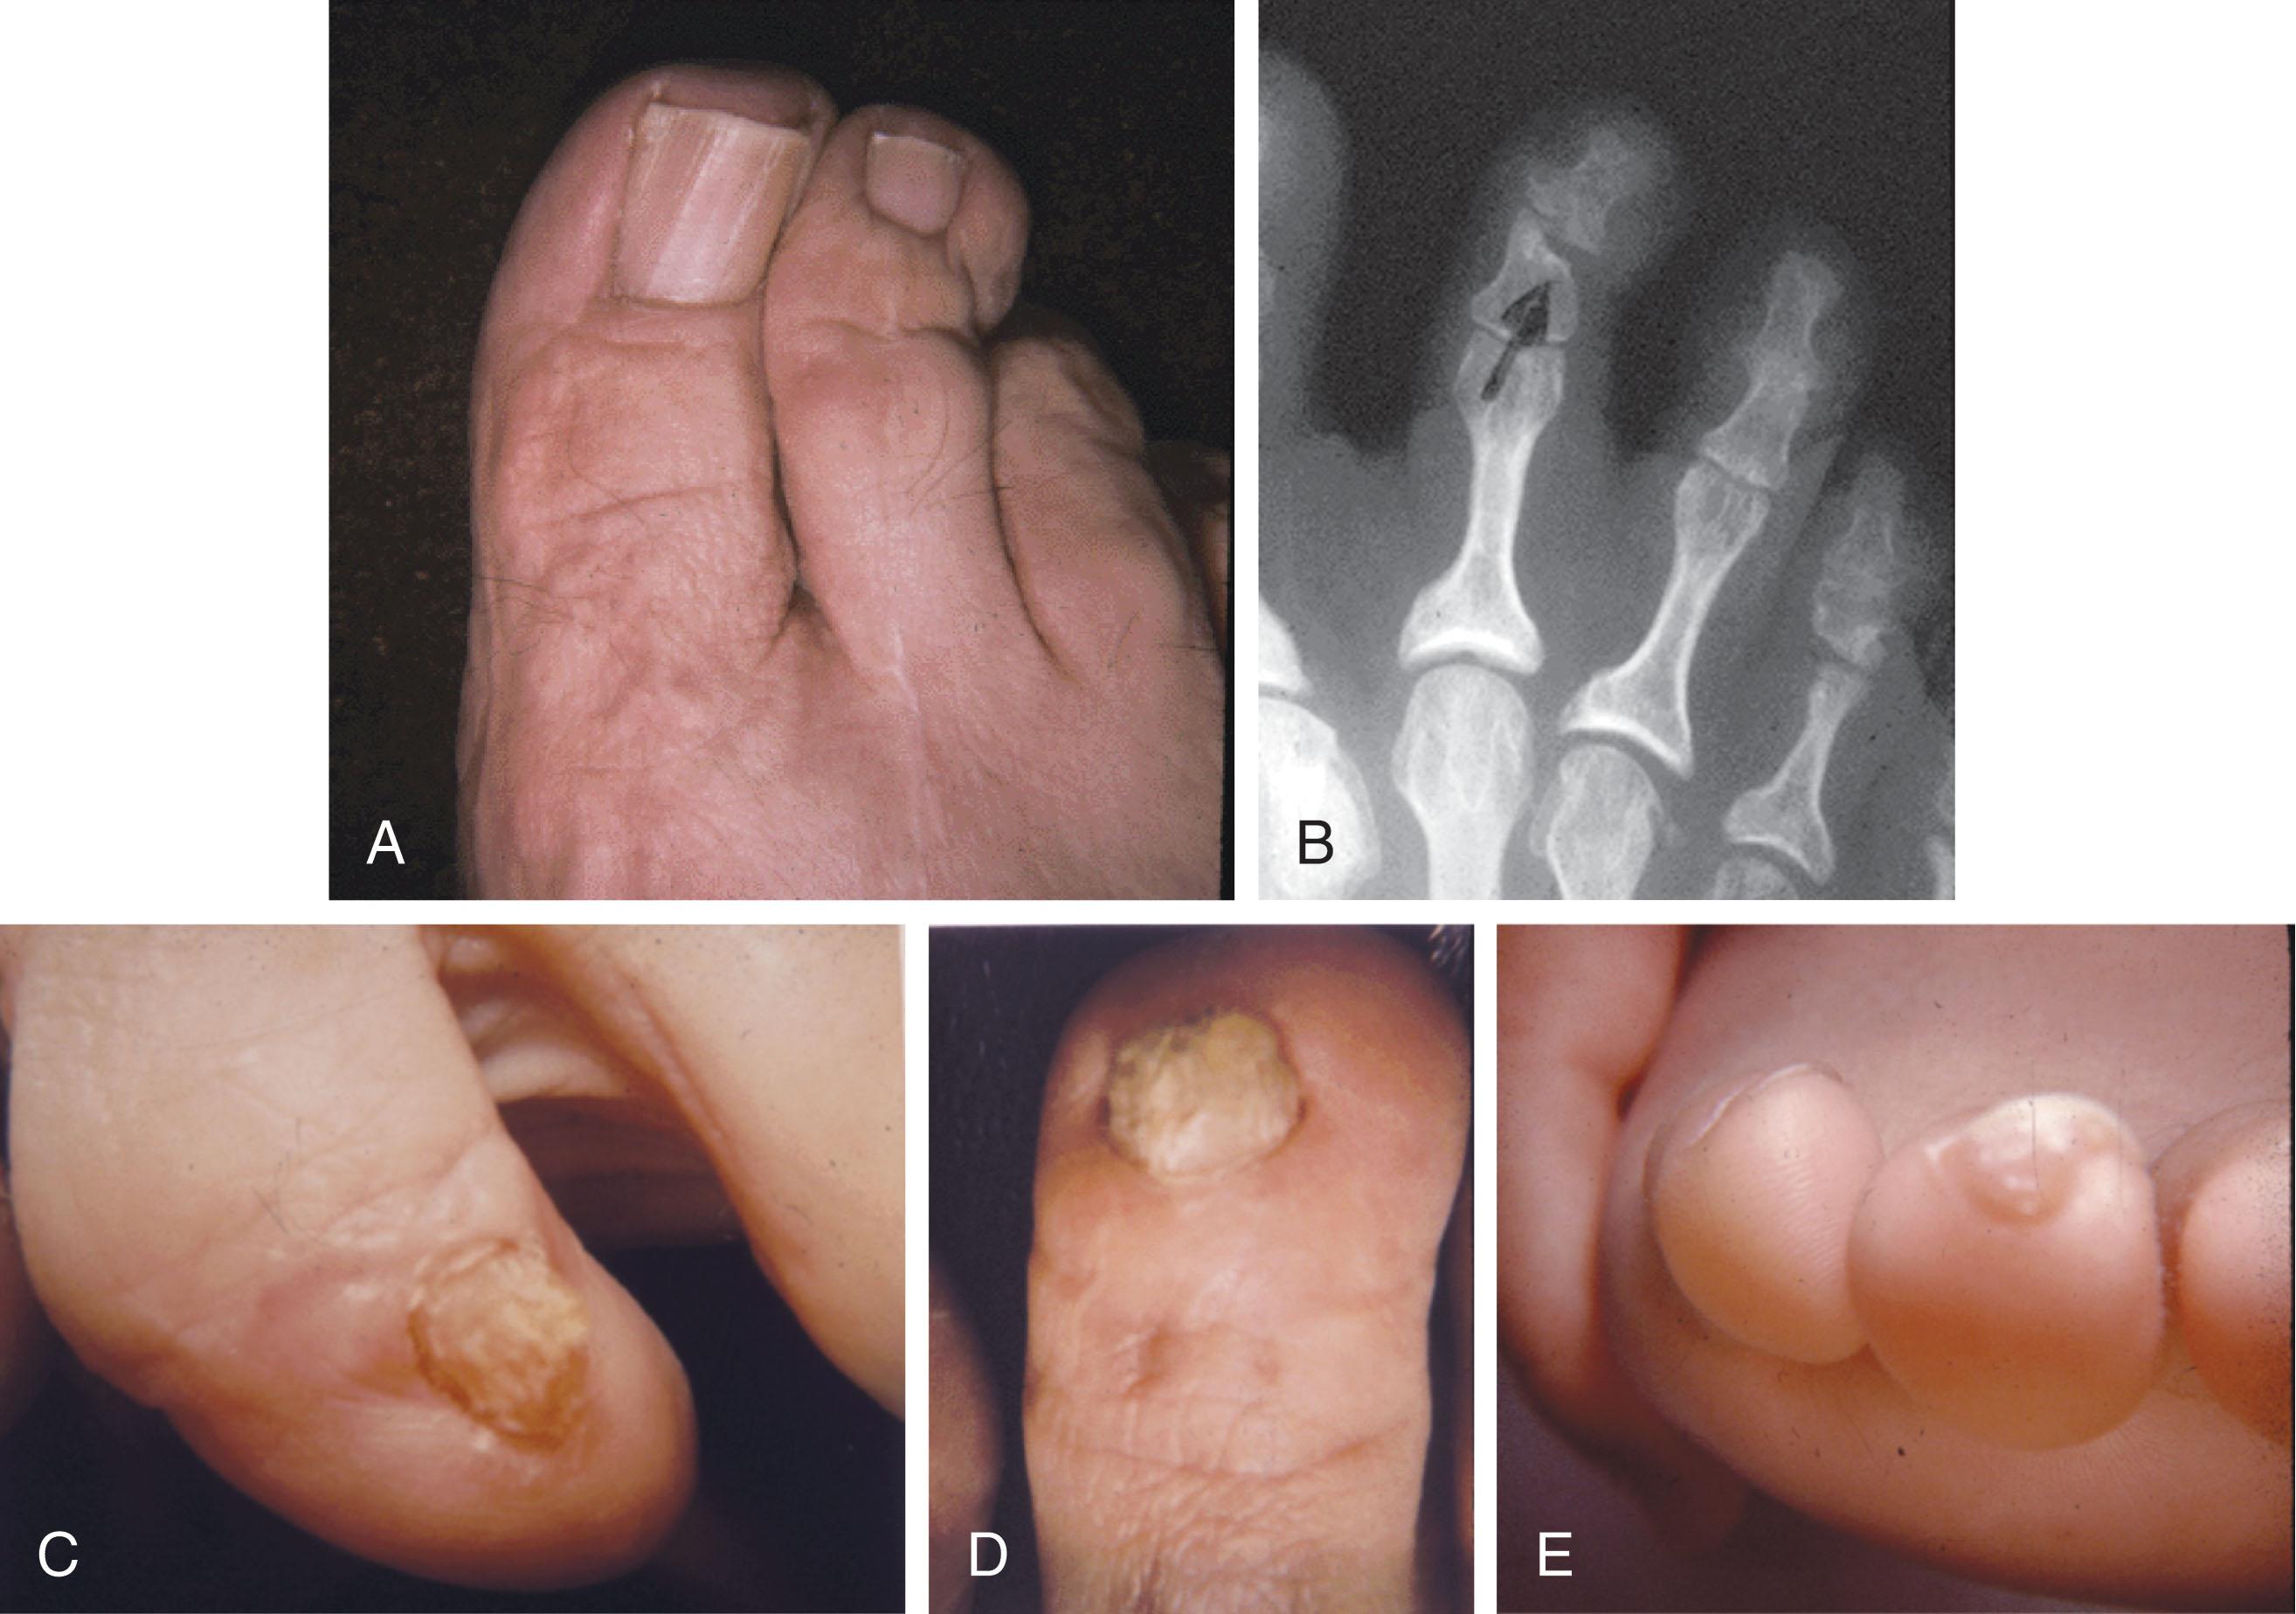

Fig. 9-1, A , Mallet toe deformity with plantar flexion contracture of the distal interphalangeal (DIP) joint. B , Radiograph demonstrating a mallet toe deformity of the fourth toe.

Fig. 9-2, Comparison of simple and complex hammer toes. A , Simple hammer toe deformity with plantar flexion contracture of the second proximal interphalangeal (PIP) joint. The first toe is held down to allow visualization of the second toe. B , Complex hammer toe with hyperextension deformity of the metatarsophalangeal (MTP) joint and plantar flexion contracture of the PIP joint. Although this is similar to a claw toe, it typically involves only one digit.

Fig. 9-3, A , Complex hammer toe deformity involving metatarsophalangeal and proximal interphalangeal (PIP) joints of the second toe. B , Lateral radiograph demonstrating severe flexion deformity of PIP joint.

Fig. 9-4, A and B , Photographs of claw toe deformities involving hammer toe deformity associated with dorsiflexion of the metatarsophalangeal joint, and flexion of the distal interphalangeal (DIP) joint and associated painful callus and nail deformation (red arrow) . Also note the associated IP flexion contracture of the great toe.